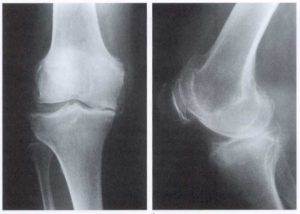

Для постановки диагноза назначается проведение рентгенологического исследования пораженного сустава. При описании снимка врач обращает внимание в основном на наличие остеофитов на костях, сужения щели сустава, визуальные изменения толщины костей. При визуальном осмотре подтверждается наличие боли, ограничения двигательной активности и видоизменения суставной сумки.